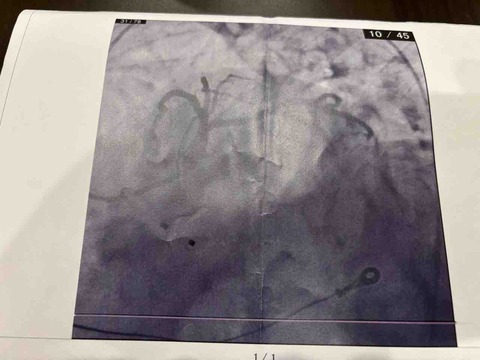

実録!心筋梗塞?おまけ

そう言えば救急搬送後の心臓部の写真がありましたよっと。血管が写ってない?※右下に器具みたいのが見える?血流が戻った写真?どうやらあまり詰まるこ···